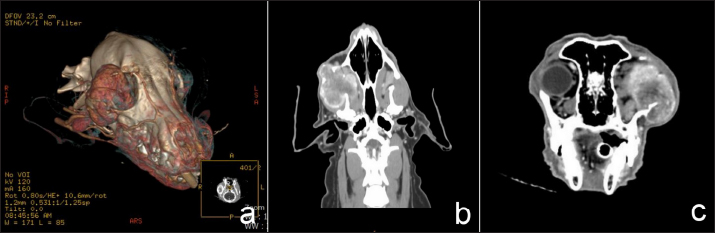

CT for 4 weeks after the surgery demonstrated a heterogeneous mass effect (0.6 × 0.8 cm) in the right caudal maxilla area which extended to part of the right retrobulbar mass with hyper density contrast enhancement (Fig. 4). There was no detection of soft-tissue nodules in the lungs. The radiation treatment plan aimed to control retained mass and micro metastasis.

Fig. 4. Transverse (a) and dorsal (b) computed tomographic images in the right retrobulbar, maxilla, zygomatic, and temporal areas with mass effect at right caudal maxilla area, extending to part of right retrobulbar mass with hyper density contrast enhancement.